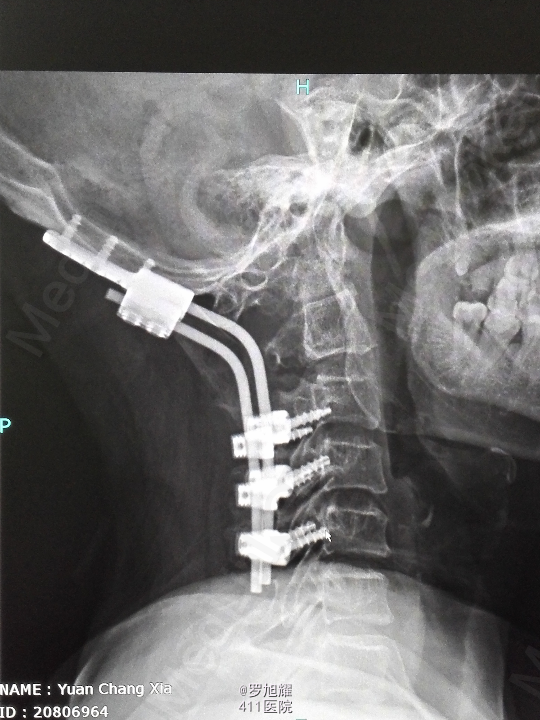

诊断为:颈椎先天畸形、颈2/3椎间盘突出伴不全瘫。 因寰枢关节退变,颈椎活动已部分受限,而且枢椎椎板棘突缺如,稳定性差,决定后路减压枕颈融合。

因寰枢关节退变,颈椎活动已部分受限,而且枢椎椎板棘突缺如,稳定性差,枕颈融合虽然造成颈部活动受限,但是稳定性好,避免脊髓再次损伤。本例手术后半月上肢麻木明显改善,躯干和下肢麻木尚待恢复。